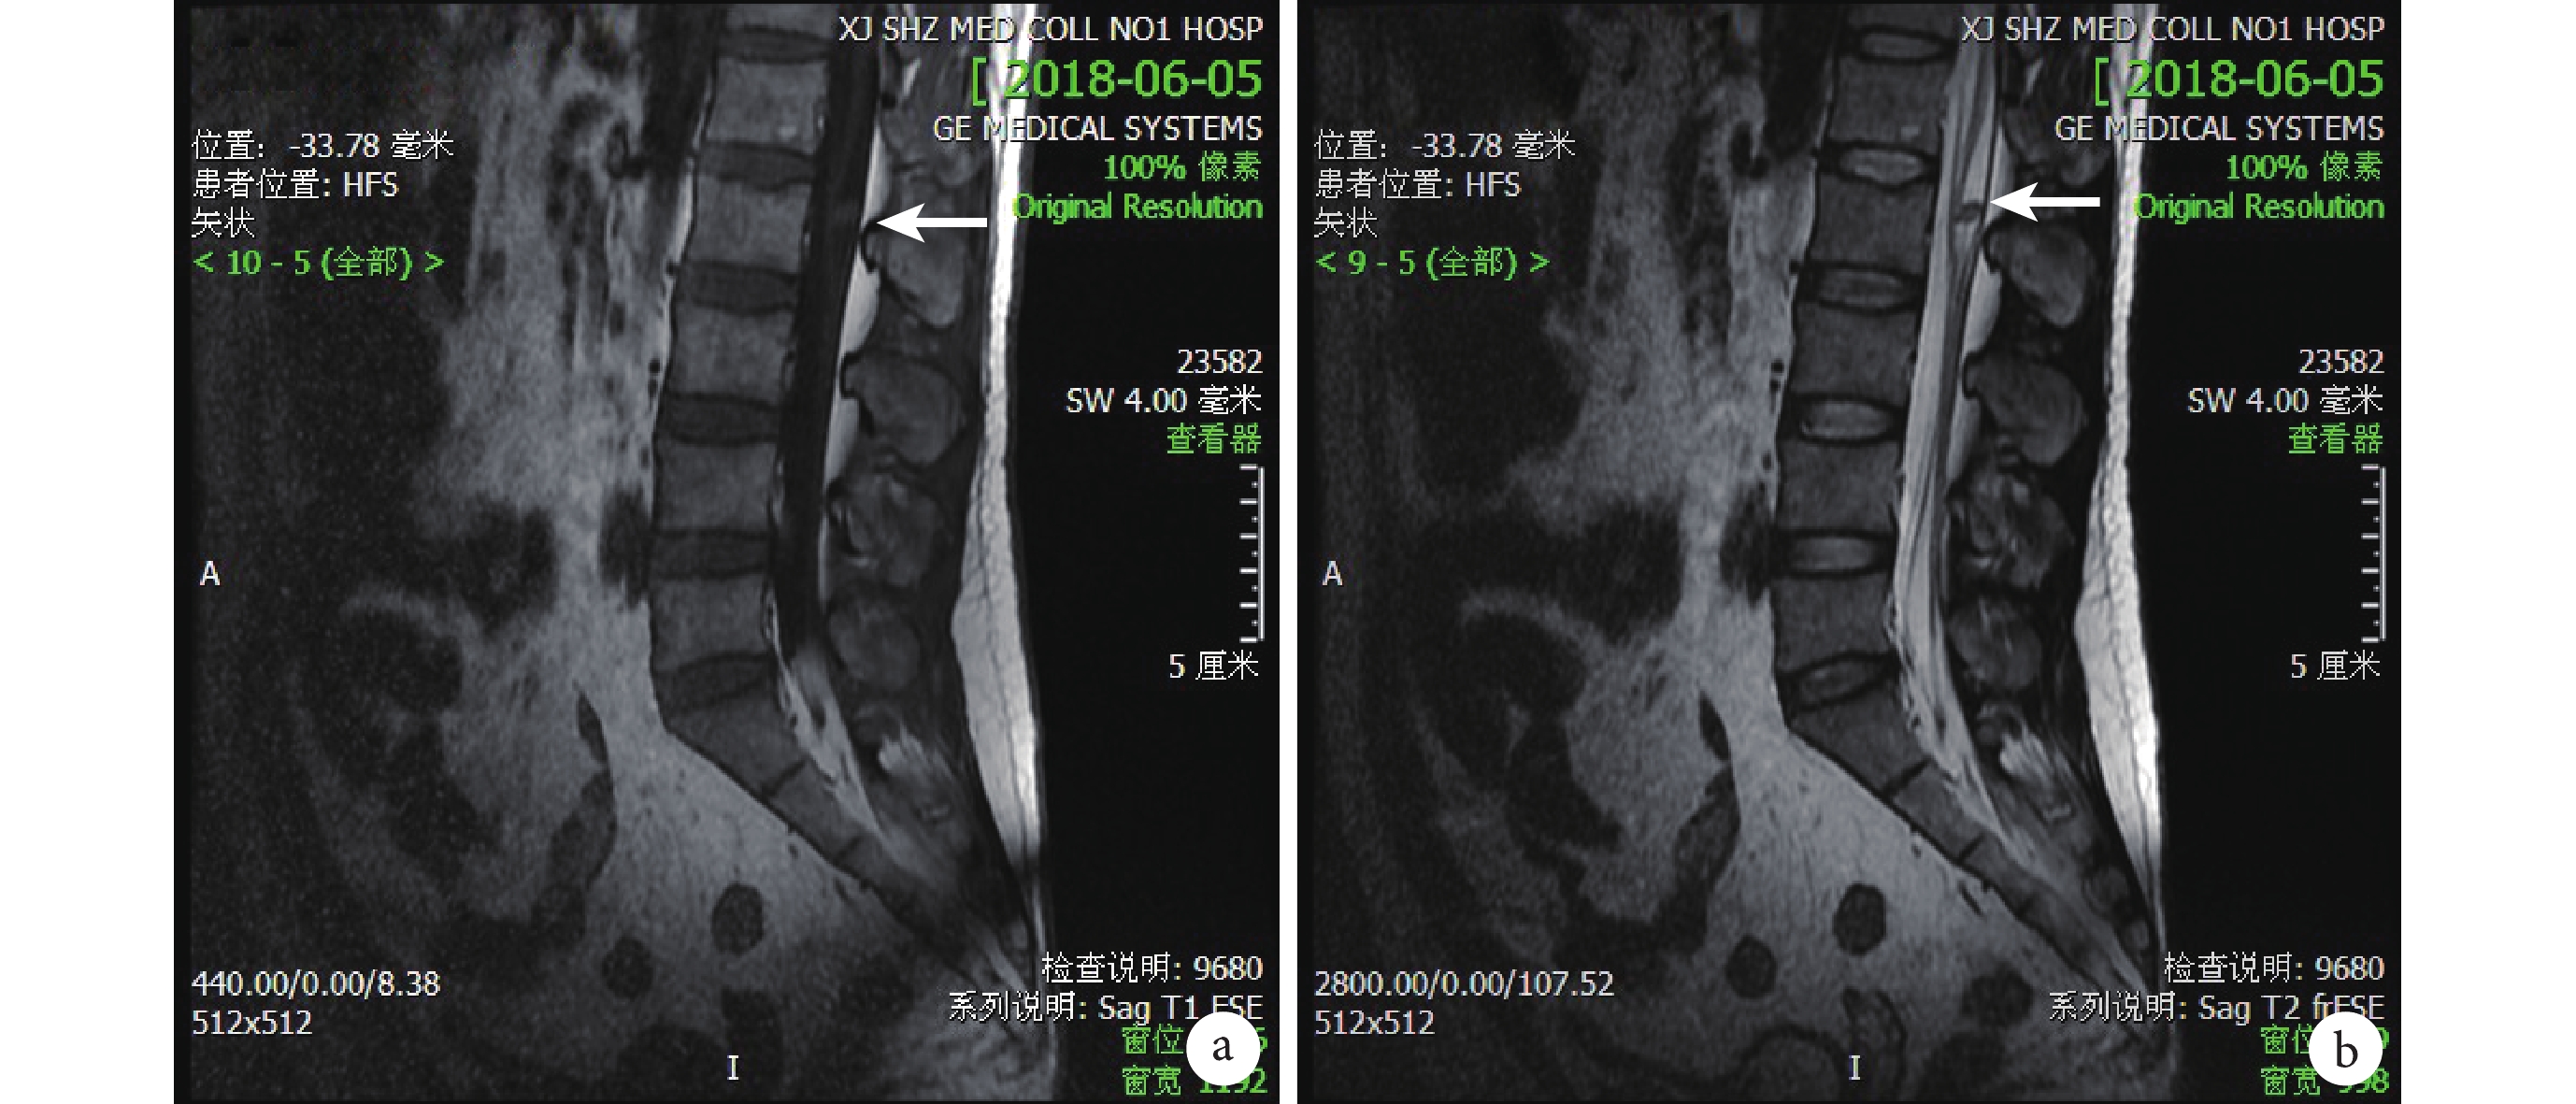

圖1

入院當天患者腰椎 MRI

a. 腰 2 椎體水平椎管內髓外硬膜下見結節狀異常信號(白箭),T1 加權像呈等信號;b. 腰 2 椎體水平髓外硬膜下結節狀異常信號(白箭),T2 加權像呈低信號,最大截面約 9 mm×5 mm,境界清楚,相應水平脊髓受壓